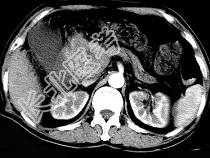

- 单项选择题男,50岁, 黄疸进行性加重、腹部胀痛不适、食欲减退、体重减轻、上腹部可触及肿块,CT如图, 最可能的诊断是 ( )

A、胰头癌

B、转移瘤

C、慢性胰腺炎

D、急性胰腺炎

E、腹膜后淋巴瘤